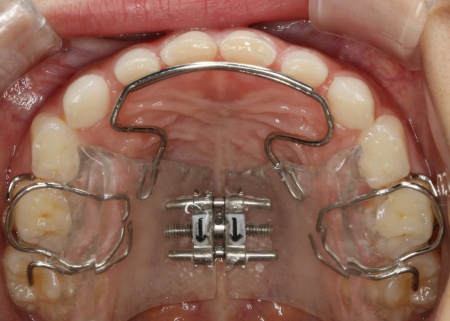

まずは上顎に「バイオブロック(BB1)」という装置を装着します。

バイオブロックとは、上顎の骨を前方に成長させることを目的とした、乳歯列期のお子様に適した矯正装置です。この装置により、上顎の骨の成長を促して反対咬合の改善を図りました。

続いて下顎には、顎の幅を広げて歯が並ぶスペースを確保しながら、上下の噛み合わせのバランスを整える役割をもつ「拡大床」という装置を装着しました。

治療中